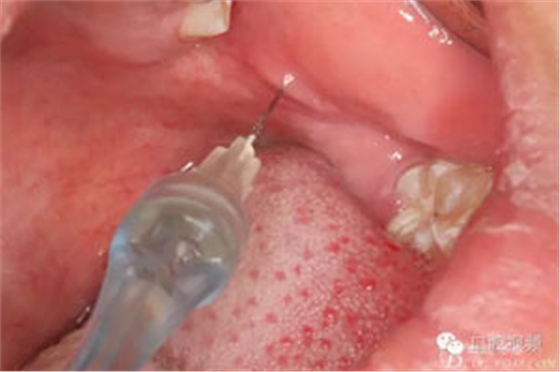

圖4.局部阻滯麻醉